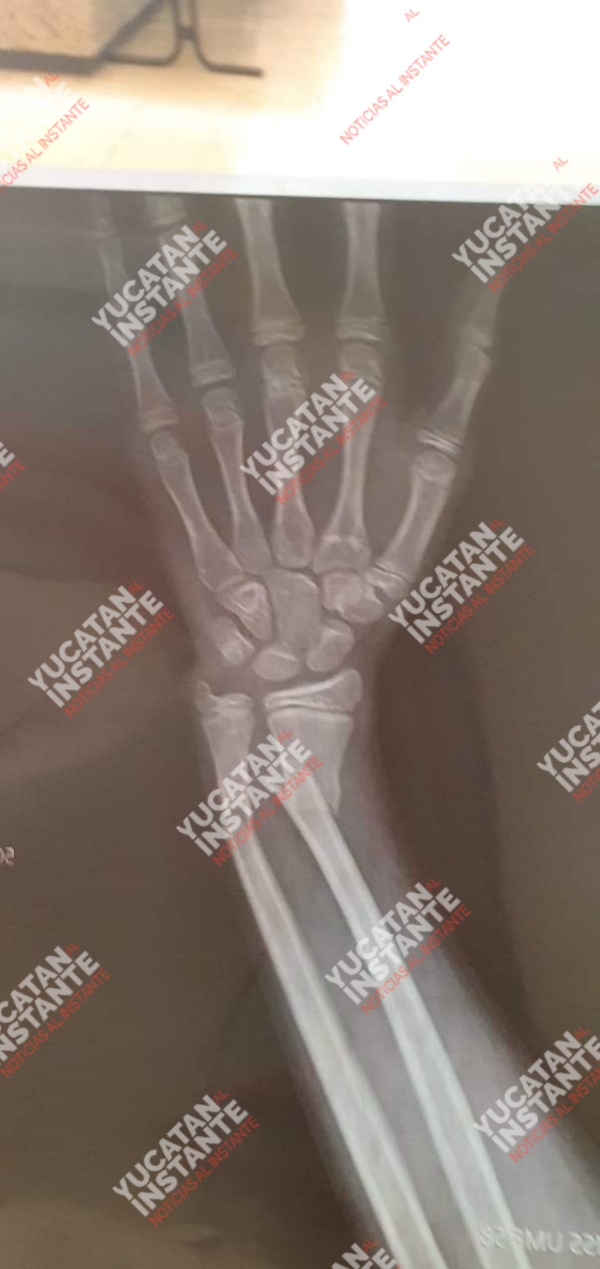

“En días pasados el alumno de segundo grado, Luis M.C.T., mi hijo, fue agredido en el interior de dicha escuela por otra persona ocasionandole fractura doble del brazo izquierdo. Cabe señalar que este caso de bullying ya traspasó los límites desde hace tiempo y la escuela no le da la seriedad que amérita”, mencionó.

Continuó, que dos días después del incidente, durante el proceso para que lo operen a su hijo, “mi esposa y yo fuimos a la escuela para que nos den una explicación de lo sucedido y resulta que ya tenían hasta un reporte por parte de la directora/subdirectora completamente distinto a la versión de mi hijo. En dicho reporte estaba asentado que el afectado se cayó sólo en una actividad, la cuál, es mentira ya que mi hijo asegura que lo estaban  molestando por otro alumno de otro grado en donde lo empujó a propósito y con fuerza, a tal grado que al caer se fractura el brazo (fractura doble)”, enfatizó.